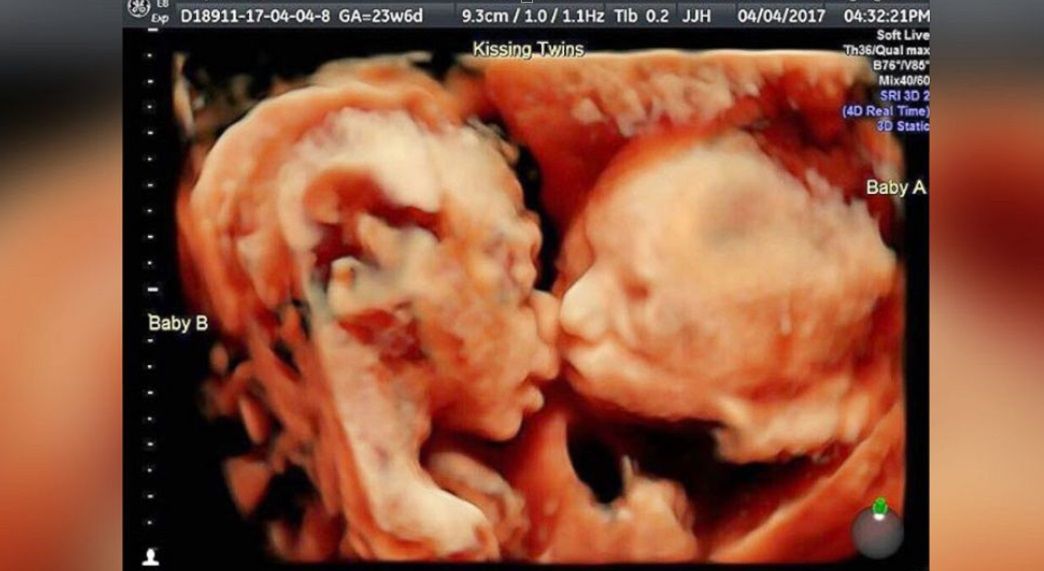

Diane McLaren, Brytyjka, spodziewała się bliźniąt. Jakie było zdziwienie położnych i lekarzy, gdy dwójka dzieci urodziła się w tym samym czasie. Medycy zgodnie uważają, że nie zdarza się to często i mówią wprost: to medyczny fenomen.

Kiedy rodzą się dzieci z ciąży bliźniaczej, zazwyczaj jest tak, że najpierw na świecie pojawia się jedno z nich, a dopiero później drugie. Różnice w czasie przyjścia na świat wynoszą zwykle kilka minut, choć zdarza się, że może to być kwestią kilku godzin.

Diane McLaren oraz jej małżonek Danny z niecierpliwością oczekiwali narodzin bliźniąt,, które otrzymały imiona Micky i Molly. Poród był fizjologiczny i kiedy głowa jednego dziecka znalazła się w kanale rodnym kobiety, świeżo upieczona mama usłyszała, że ma mocno przeć. Wówczas obok głowy chłopca pojawiły się... nogi drugiego dziecka.